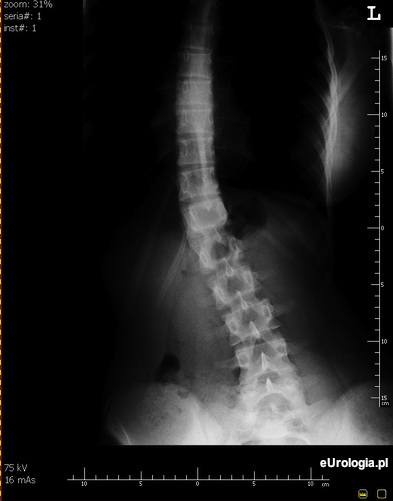

Fot. Skolioza.

W rzadkich przypadkach u pacjentów ze skoliozą może dochodzić do zaginania moczowodu co skutkuje kolkowymi bólami okolicy lędźwiowej.